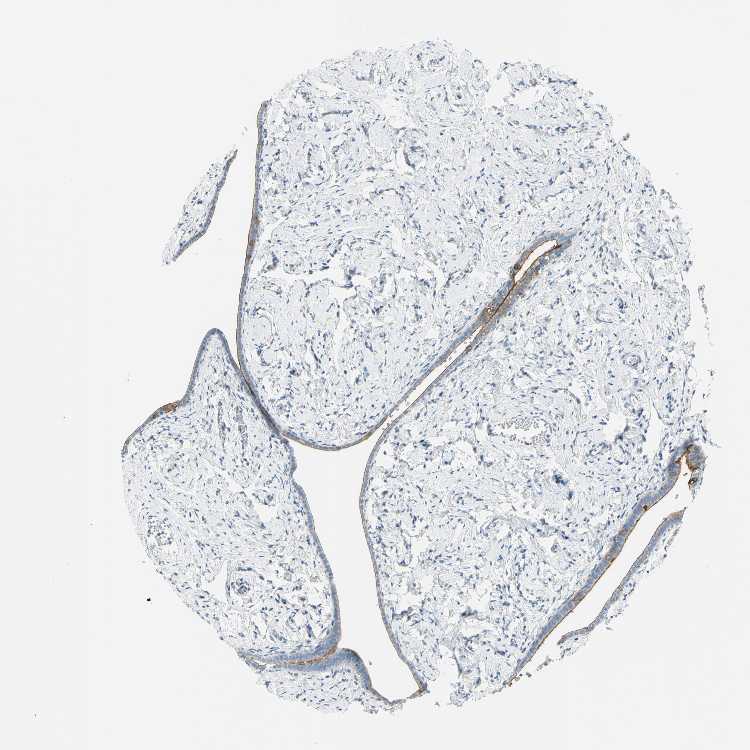

TISSUE PRIMARY DATA FALLOPIAN TUBE Show tissue menu

FALLOPIAN TUBE - Antibody stainingi

Antibody staining in the annotated cell types in the current human tissue is reported as not detected, low, medium, or high, based on conventional immunohistochemistry profiling in selected tissues. This score is based on the combination of the staining intensity and fraction of stained cells.

Each image is clickable and will lead to virtual microscopy that enables deeper exploration of all samples and also displays staining intensity scores, fraction scores and subcellular localization as well as patient and tissue information for each sample.

Antibody HPA004179Antibody HPA007235Antibody HPA008855Antibody CAB000036Antibody CAB001986Antibody CAB080102Antibody CAB080103

Glandular cells HighMediumHighHighMediumHighHigh